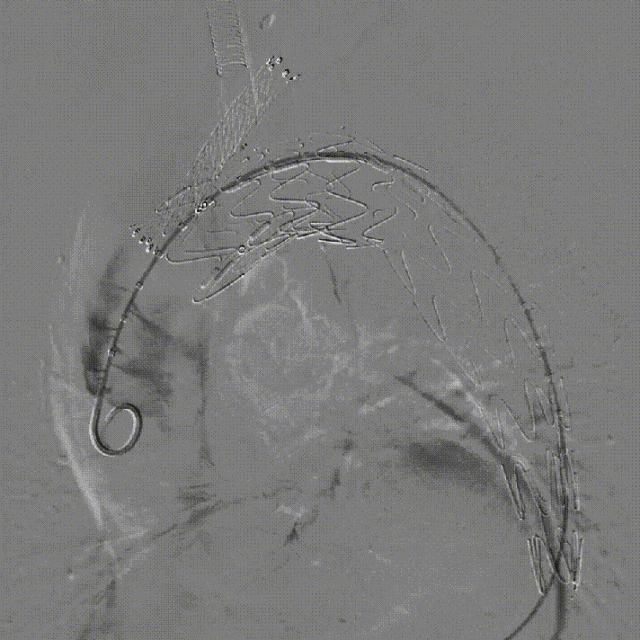

第二次术前造影,证实为LSA所致Ⅱ型内漏

LSA置入覆膜支架后造影,内漏消失